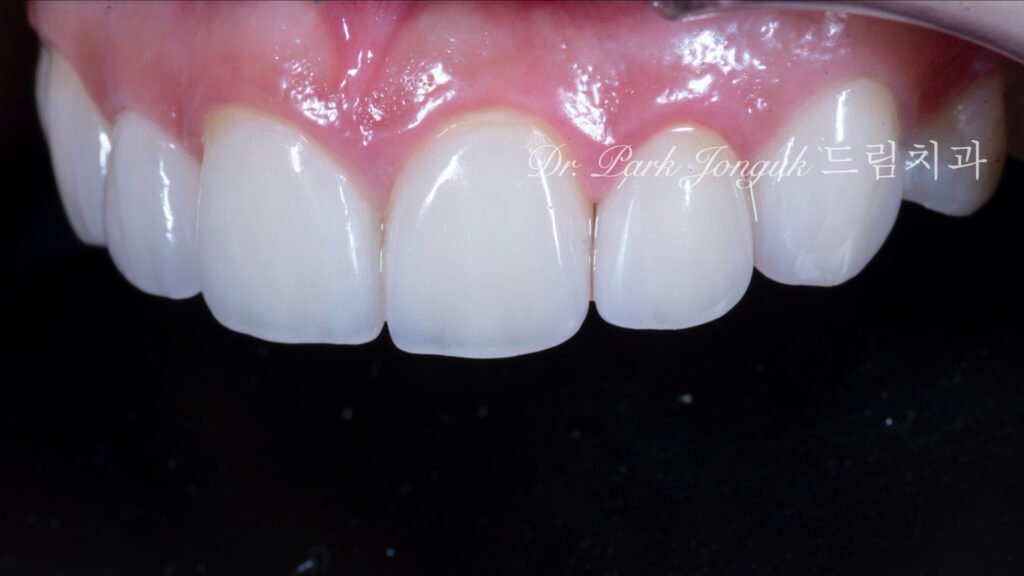

완성된 라미네이트는 초기 진단에서 설정한 모든 목표를 달성했습니다.

치아 간 비율: 왜소측절치는 정상 크기로 확대되었고, 비대했던 중절치는 적절한 크기로 축소되어 전체적으로 조화로운 비율이 만들어졌습니다. 중절치:측절치 비율이 생리학적 이상 범위에 도달하여, 더 이상 특정 치아가 유독 크거나 작아 보이지 않습니다.

비후 치근 문제의 해결: 중절치 치경부에 적용된 옐로우 스테인이 예상대로 작동했습니다. 굵은 치근으로 인한 두툼한 인상이 색상 그라데이션을 통해 자연스러운 뿌리 형태로 인식됩니다. 실제로 치근의 물리적 두께는 변하지 않았지만, 시각적으로는 자연 치아와 구별이 어려울 정도로 개선되었습니다.

심미적 통합: 전체적으로 인위적인 느낌 없이 자연스러운 치열로 보입니다. 치경부의 색상 변화, 표면의 미세한 질감, 적절한 투명도 등이 조화를 이루어 “라미네이트 했다”는 인식을 주지 않습니다.